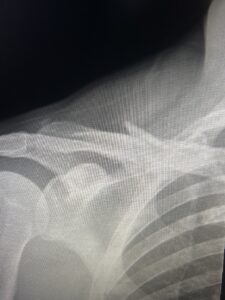

About 4 miles into the ride, I clipped my son’s rear tire and went down hard. I knew before I hit the ground that I was about to break my first bone. I landed forcefully on my shoulder and head. When I stood up, I could feel my collarbone moving in ways God never intended.

I try to make much more specific requests and prayers since that accident. I really messed up my shoulder! My clavicle was broken into 8 pieces, I tore my biceps tendon, had a concussion, and an enormous road rash that tore flesh off my leg.